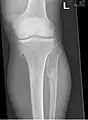

It is characterized by the growth of cartilage-capped benign bone tumours around areas of active bone growth, particularly the metaphysis of the long bones. Typically five or six exostoses are found in upper and lower limbs. Image depicts adult regrowth after knee replacement.

The diagnosis of HMO is based upon establishing an accurate correlation between the above-mentioned clinical features and the characteristic radiographic features. Family history can provide an important clue to the diagnosis. This is supplemented by testing for the two genes in which pathogenic variants are known to cause HMO namely EXT1 and EXT2. A combination of sequence analysis and deletion analysis of the entire coding regions of both EXT1 and EXT2 detects pathogenic variants in 70–95% of affected individuals.[3][4] The hallmark of radiographic diagnosis is the presence of osteochondromas at the metaphyseal ends of long bones in which the cortex and medulla of the osteochondroma represent a continuous extension of the host bone. This is readily demonstrable in radiographs of the knees.[3][1]